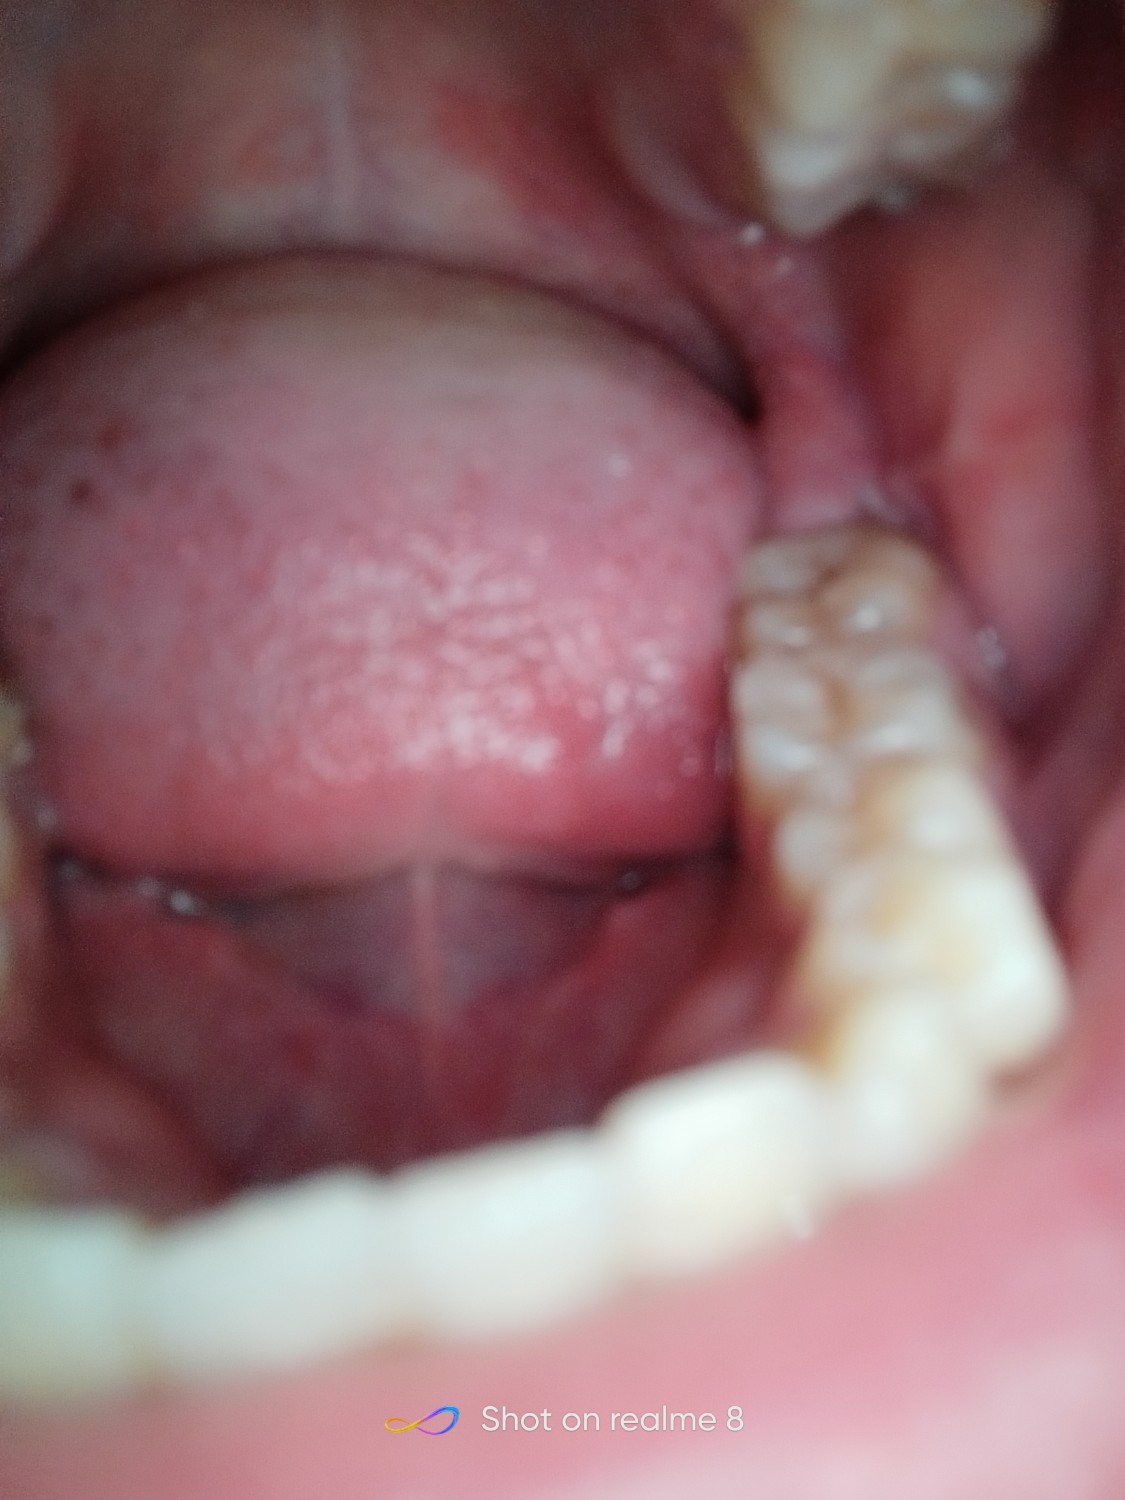

อย่างงี้ฟันคุดใหมครับเหมือนเหงือกจะแยกออกจากกันด้วย

วันแรกที่เป็นคือปวดมากครับ กลืนน้ำลายก็ลำบาก ผ่านมาประมาณ2-3วันแล้ว อาการดีขึ้น ไม่ปวดมาก แต่ตรงเหงือกส่วนที่บวม มันชนกับฟันกรามซี่บนตลอด เวลาจะเคี้ยวข้าว หรือเวลาหุบปากไว้เฉยๆ รำคาญสุดๆ ผมเลยอยากรู